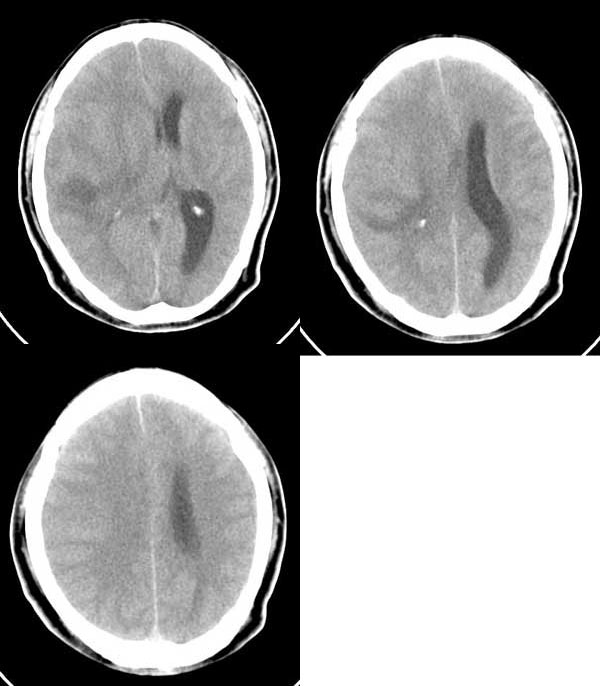

CT00503 颅内占位(病理结果3天后公布)

头疼3个月,加重5天

右颞顶叶较大囊实性肿块,可见结节及花环样强化,瘤周水肿和明显的占位效应,多考虑胶质瘤.3-4级星形细胞瘤可能性最大.

右侧顶叶占位性病变,右侧顶叶胶质瘤。

右颞顶叶囊实性肿块,占位效应明显,轮廓尚清,累及皮层,瘤周水肿不明显,病灶偏心性坏死或液化,形态不规则,增强后实性部分中等强化,坏死区未强化,瘤周及瘤内有粗大血管影。

考虑1、星形细胞瘤1-2级或毛细胞型星形细胞瘤(1级);2、转移瘤